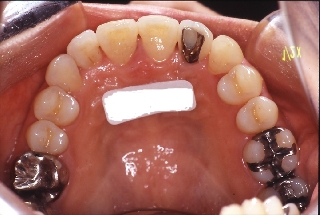

インプラント治療の為の矯正治療症例2

初診時年齢52歳。上顎前歯部欠損部インプラント治療前の咬合改善目的に来院。

当院にて前歯部の被蓋の改善を行った。

インプラント治療は専門医にて行った。

上顎 上顎 上顎